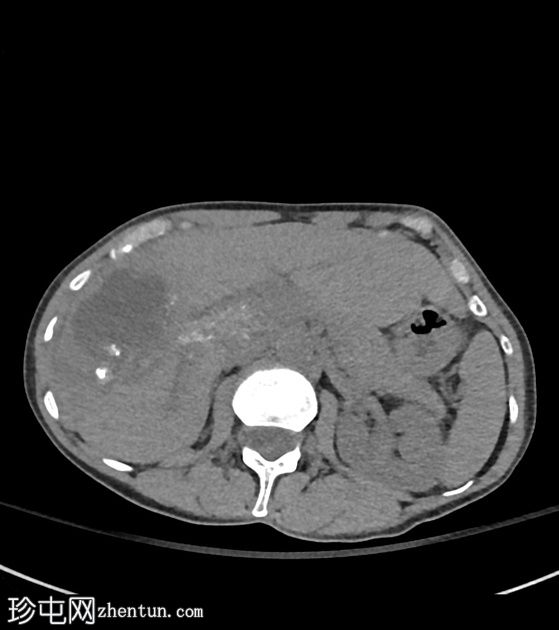

CT扫描

轴向

非造影

肝段VIII区中心可见一囊性坏死灶,边缘不规则,周围可见粗钙化,造影后无明显强化。轻度包膜回缩及邻近灌注改变。肝穹窿内可见其他较小的卫星囊性灶和多处粗钙化。肝门部可见浸润性组织,部分钙化,导致门静脉轻度狭窄和右侧肝内胆管轻度扩张。

CT表现符合肝泡包虫病。